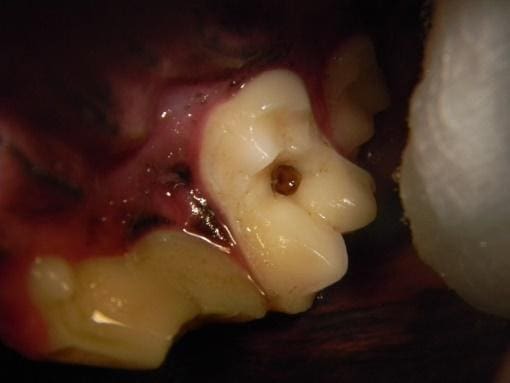

Figure 2. Two examples of complicated crown fractures that exposed the pulp of the tooth. (A) The red dot on the crown of the tooth indicates pulp exposure. (B) The start of oral surgery to extract a fractured tooth. In this step, the gingiva and oral mucosa are being elevated off the underlying bone. The bone is then removed to expose the roots.

(A)

(B)